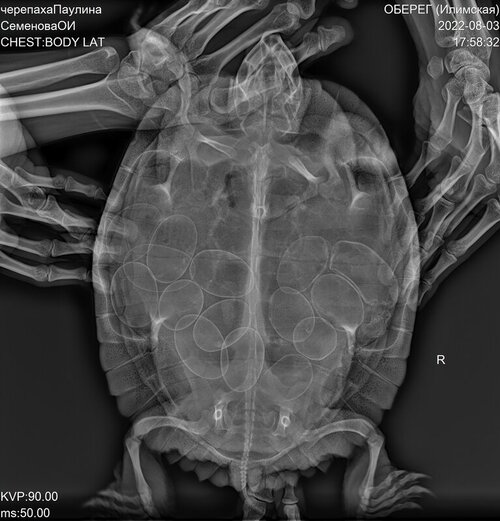

10 лет. Черепаха откладывает яйца последние 6 лет. Начинает беспокойно себя вести в конце марта-апреле. С середины июля начинает нестись. В этом году поведение изменилось. Также начала беспокойно себя вести в апреле, потом успокоилась, сейчас тоже ведёт себя спокойно. Яиц до сих пор нет. Сделали рентген. Смущает вид верхнего яйца справа. Оно как-будто деформировано и рядом какой-то подтек. Могло ли яйцо повредиться в черепахе и что с этим делать?

@Avonemes врач ответила, что есть несколько аномальных яиц, в том числе то, что Вы указали. Если бы лопнуло - уже были бы признаки желточного перитонита. Но черепаху очно показать стоит, возможно получится по узи посмотреть точнее и сделать стимуляцию, чтобы она снеслась.

@Avonemes либо через неделю ещё раз сделать рентген. Но лучше всё-таки сходить на приём.